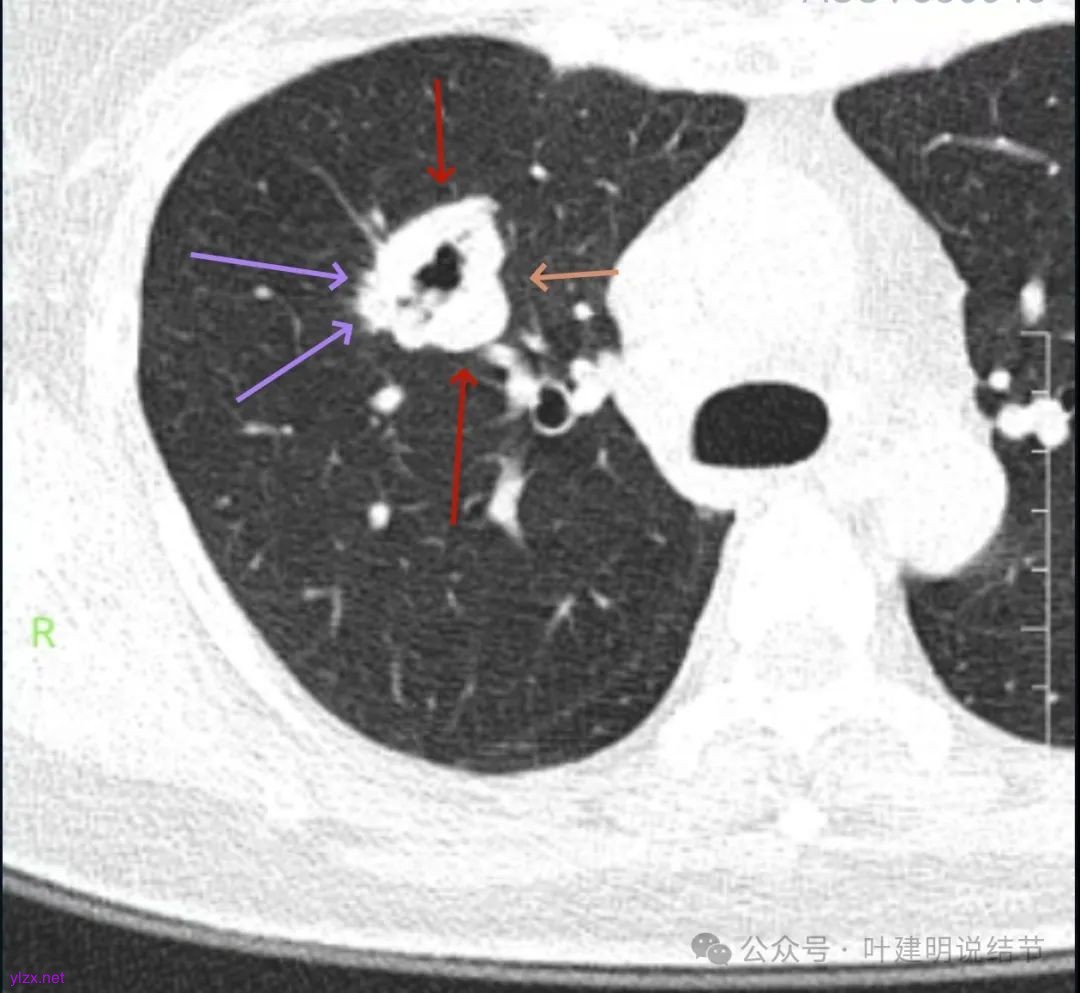

影像展示与分析:

你的右上叶这个病灶基本上肯定是肺癌,要尽快处理。从影像上看有以下特点:1、整体轮廓清楚,不似普通炎症的周围有晕或阻塞性改变;2、边缘明显的浅分叶,总体上的感觉膨胀性明显,不管哪个层面看上去都是鼓鼓的;3、边缘区域有磨玻璃成分而且也是分叶状的;4、部分层面见血管进入;5、空腔病灶的壁厚薄不均,内壁不光滑。我考虑中低分化肺癌,由于腔静脉旁有明显肿大淋巴结,需要进一步完善增强CT以及PET-CT检查以明确有无远处转移,是否仍可手术治疗(从病灶本身来说是可以肺叶切除治疗的)。要尽快处理。意见供参考!